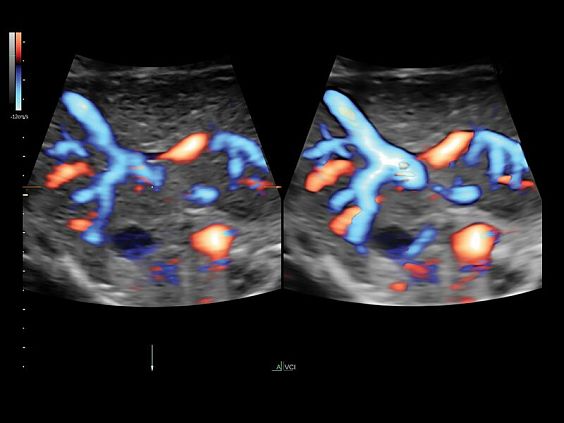

Клинические изображения

• Тканевой допплер

• Высокочувствительный допплер (HD-Flow)

• Постоянно-волновой допплер (CWD)

• Реалистичный объёмный кровоток в режиме ЦДК (Radiantflow)

Voluson E10 поддерживает инновационные технологии формирования изображений — HDlive Silhouette и HDlive Flow, которые позволяют увидеть мельчайшие детали. Алгоритм SonoRenderlive упрощает рабочий процесс и дает возможность реконструировать изображение поверхностей, определяя область перехода между тканью и жидкостью.

• Технология HDlive Flow — повышает реалистичность визуализации сосудистых структур, улучшая восприятие глубины (по сравнению с традиционным цветовым допплером и функцией HD-Flow).

• SonoAVC (Sonography-based Automated Volume Count) — инновационный инструмент для визуализации и измерения гипоэхогенных структур, в том числе фолликулярного аппарата и мозга плода, а также для выполнения соногистерографии.